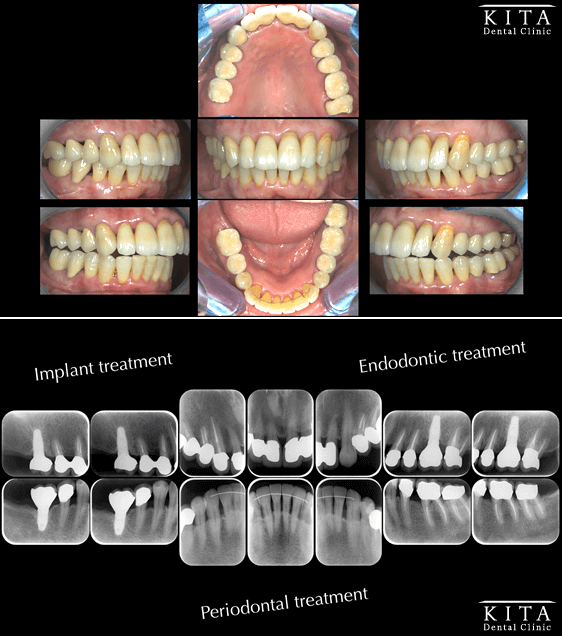

①術前の状態

全体的に中等度以上の歯周病に罹患しています。

ご本人の自覚症状はほとんどなく、主訴は審美的な改善でした。

②治療終了後の状態

全額的な治療を行い歯周病の進行を止めることに成功しています(治癒)。

ブラッシングの技術も安定し良好な予後が期待できます。

主訴であった審美的な問題も改善しています。